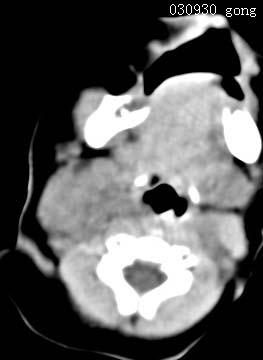

以下是引用zjzjr在2008-12-18 11:20:00的发言:[br]右颈部软组织肿块,性质待定(神经源性肿瘤等排),上下径较长,不太支持肿大淋巴结.